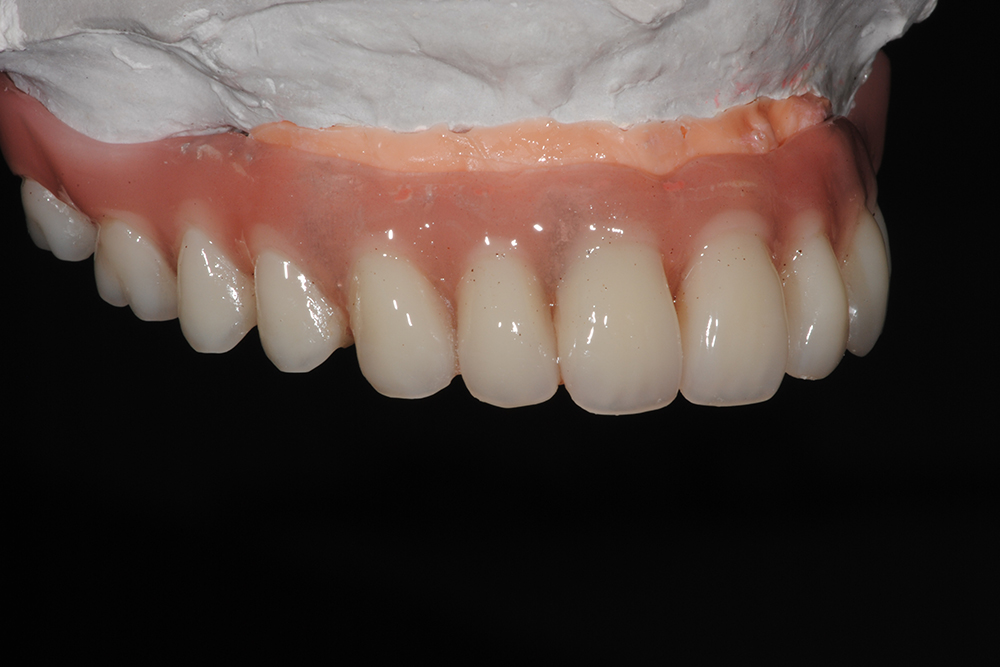

Ripristino dell’arcata superiore su overdenture su barra